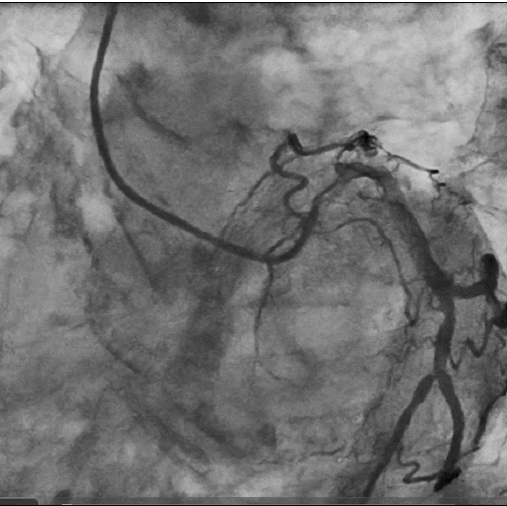

造影: